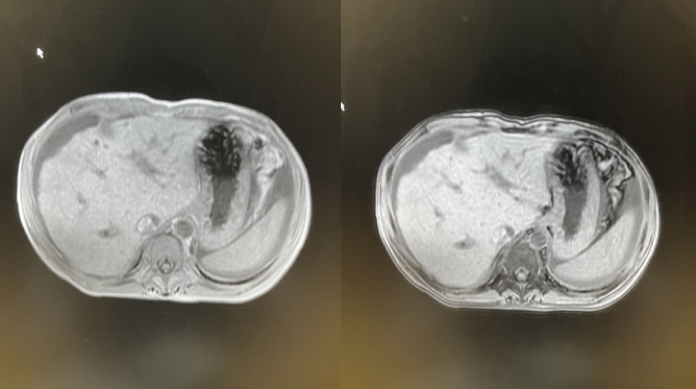

2020年7月21日术后MR检查:下腔静脉肝后端及双肾水平处,左肾静脉、右肝门区扩张静脉、肝内部分侧枝血管内栓子形成(图2)。

图2.2020年7月21日术后MR